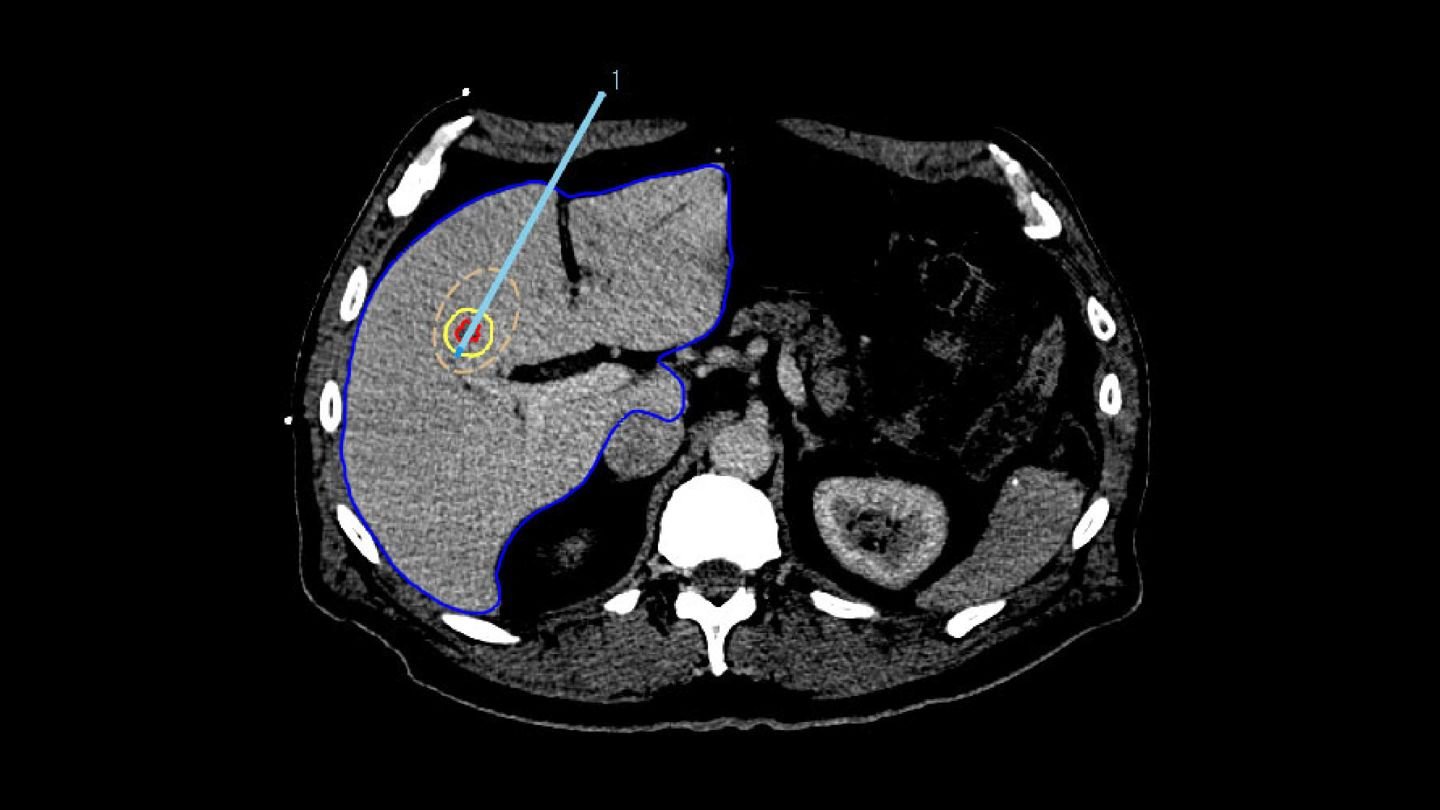

2. TARGETING

To ensure accurate applicator placement before treatment, the segmented tumors from the planning phase are mapped using deformable registration, allowing for a visualization of the anticipated tumor position. Additionally, the ablation zone can be estimated based on the applicator parameters, such as its current position, selected power, and ablation duration.